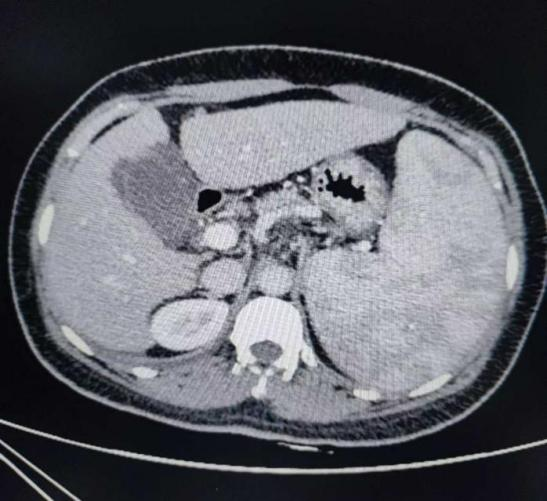

患者蒋女士今年50岁,从2018年至今已经有五次食管胃底静脉破裂出血病史,做3次胃底静脉硬化治疗。半月前胃底再次出血,入住自治区南溪山医院消化内科。经评估病情后考虑患者乙肝后肝硬化巨脾脾功能亢进,白细胞、红细胞、血小板“三系”减低,多次硬化剂治疗再次出血,有手术指征,经肝胆胰脾外科会诊后拟全麻下行全麻行腹腔镜下脾切除术+贲门血管离断术。

术前CT检查